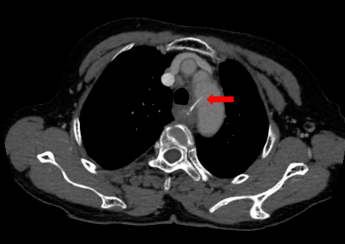

10月6日下午 , 梁奶奶来到了广州医科大学附属第二医院(简称:广医二院)耳鼻咽喉科 , 首诊医生郭镇平主任医师为进一步明确鱼刺的位置和大血管之间的关系 , 立即联系放射科行急诊胸部CT平扫+增强检查 , 值班医师阅片后发现鱼刺已穿破食管壁和胸主动脉内侧壁 , 鱼刺一直深入到主动脉腔内!

文章图片

CT图像显示:鱼刺穿破食管壁和胸主动脉内侧壁 。